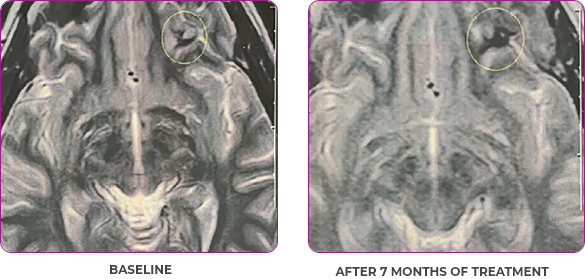

Response in primary and metastatic lesions1

MRIa imagery of the brain. Green circles indicate baseline brain metastases.1

SCAN 2: BRAIN

aMRI, magnetic resonance imaging.

MRIa imagery of the brain. Green voxels indicate decreased burden of metastatic disease; further quantified by accompanying measurement in green.1

SCAN 3: BRAIN

- Partial response to treatment that was confirmed at 2 months (34% tumor reduction)

- Grade 1 cough and Grade 2 fatigue

- Patient remains on VITRAKVI after more than 4 months of treatment